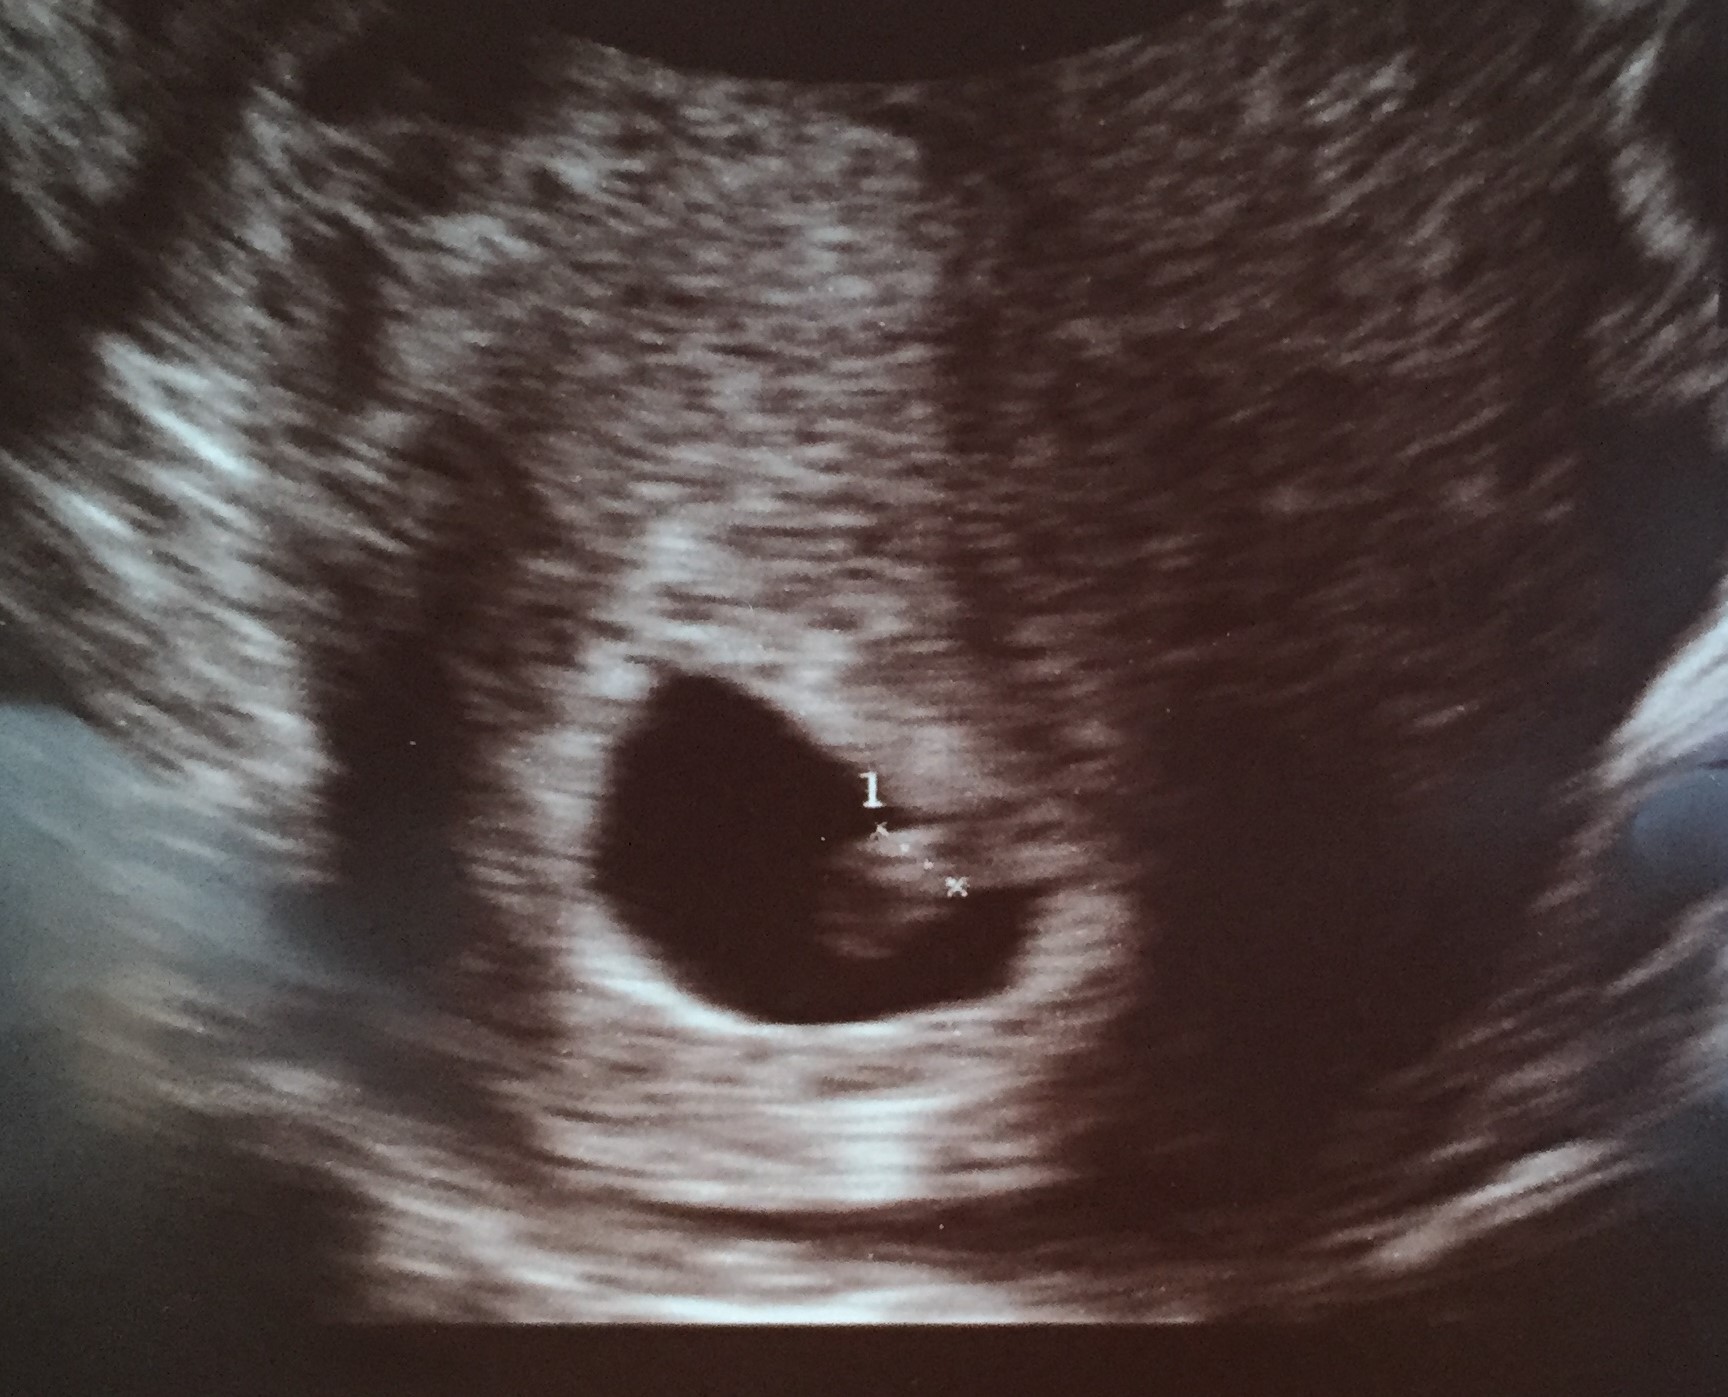

Can anyone take a guess based on these 6 and 12 week ultrasounds? thanks!